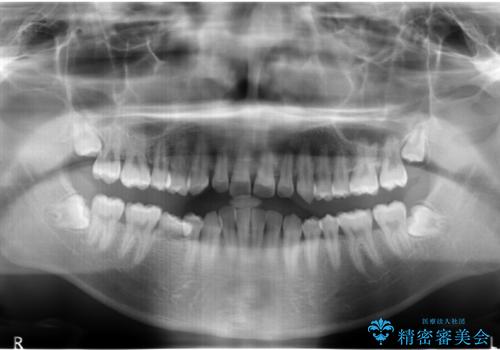

右下に乳歯が残っていましたが、後に続く永久歯がありませんでした。

乳歯も根が吸収しており長くは持たない状況でしたので、まず乳歯を抜歯し、他の歯を矯正治療で歯を並べてからインプラントで補綴しました。

先にインプラントをしてしまうと、矯正治療で周りの歯を動かす事ができなくなってしまいます。

矯正治療→インプラントの順で行います。